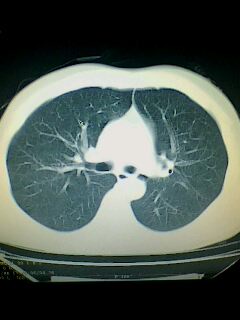

标题: CT28315:咳嗽咳痰咯血半月并胸痛 [打印本页]

标题: CT28315:咳嗽咳痰咯血半月并胸痛

1、纵膈窗效果不好,初步考虑左肺下叶感染性病灶,建议正规抗炎治疗后复查   2、右肺下叶陈旧性病灶伴局部胸膜增厚。

考虑左肺下叶周围型肺癌.图象欠清,请问病人贵更?

考虑左肺下叶周围型肺癌.

图像资料欠清,建议强化,考虑周围型肺癌。

左下肺肿块影,深分叶,考虑肺癌。

左下肺球形病灶,考虑:1:球形肺炎;2:周围型肺癌不除外,建议治疗后复查

不排除左肺下叶周围型肺癌可能!建议穿刺活检!

考虑左肺下叶周围型肺癌并阻塞性肺炎。